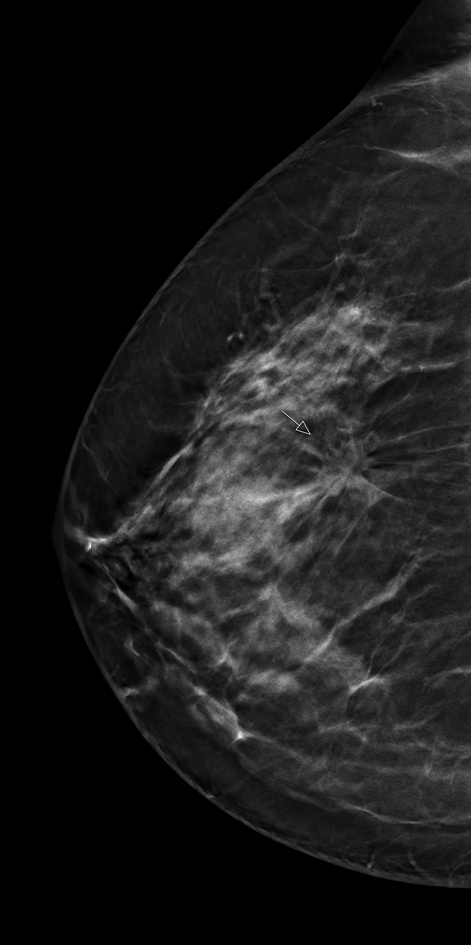

Do improvements in the digital technologies used for the early detection of breast cancer also result in increased efficiency in mammography screening? This is the question at the heart of a large-scale research project being undertaken by the Institute of Clinical Radiology at Münster University Hospital (UKM). The so-called ToSyMa study will examine whether technical developments in digital mammography towards image sectioning methods (digital breast tomosynthesis) represent a positive advance over the current standard of two-dimensional mammography screenings.

“The further development of digital mammography towards breast tomosynthesis provides technology which, by creating three-dimensional data sets, reduces potential tissue overlays in the breast and can therefore offer diagnostic advantages. The first results from the ToSyMa study are expected in late 2020, with the final results being available in 2023,” says Prof. Walter Heindel, Director of the Institute of Clinical Radiology (IKR) at Münster University Hospital. The project name is an abbreviation, derived from the English title of the study: “Digital breast tomosynthesis plus synthesised images versus standard full-field digital mammography in population-based screening”).